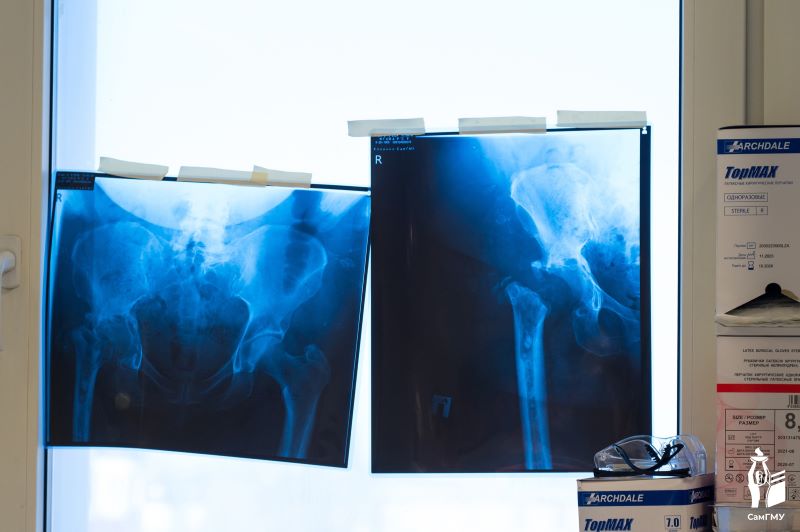

В Самарской области впервые установили пациенту индивидуальный эндопротез-спейсер

В 2022 году в одном из лечебных учреждений пациентке выполнили операцию по замене тазобедренного сустава. Однако в послеоперационном периоде у женщины неоднократно происходили вывихи головки эндопротеза. Ей провели еще одну операцию, чтобы устранить вывих, но после этого у женщины развилась перипротезная инфекция. В течение следующих лет пациентке провели несколько оперативных вмешательств, но устранить перипротезную инфекцию так и не удалось. Исправить ситуацию взялись в Клиниках СамГМУ.

Впервые в Самарской области в ходе ревизионного эндопротезирования тазобедренного сустава пациентке установили индивидуальный эндопротез-спейсер с антибактериальным покрытием. Специальное устройство — спейсер, — схоже с первичным эндопротезом и было изготовлено из костного цемента, в который добавлен антибиотик. Все это позволяет одновременно устранить инфекцию и восстановить утраченные функции сустава и ноги.

«В нашей сложной клинической ситуации мы не могли пойти по протоколу двухэтапного лечения, так как спейсер физически было невозможно зафиксировать к кости вследствие ее выраженного дефицита. Поэтому мы приняли нестандартное решение — изготовить и установить эндопротез-спейсер, индивидуально спроектированный на основе данных КТ пациентки», — рассказал руководитель Центра ревизионного эндопротезирования суставов конечностей Клиник СамГМУ, заведующий травматолого-ортопедическим отделением №2, главный внештатный специалист травматолог-ортопед Минздрава Самарской области, д.м.н. Дмитрий Кудашев.

Еще одна важная особенность разработанного эндопротеза — связанность. Это будет служить профилактикой вывихов, риск которых у пациентки очень высок.

Фото: СамГМУ